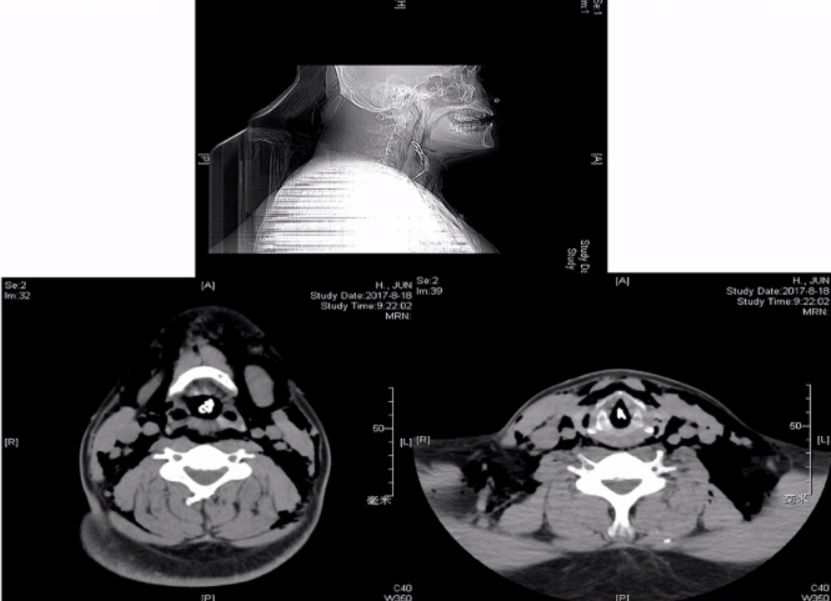

颈部CT

甲状软骨水平气道受阻,喉肿物

◆颈部CT

咽部及主支气管颈段异物,双侧颈部软组织间隙及胸壁皮下积气,气管破裂可能